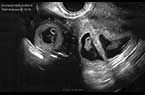

Grossesse gémellaire monozygote monochoriale biamniotique de 8 SA et 3 jours Grossesse gémellaire monozygote monochoriale biamniotique de 8 SA et 3 jours Grossesse gémellaire monozygote monochoriale biamniotique de 8 SA et 3 jours